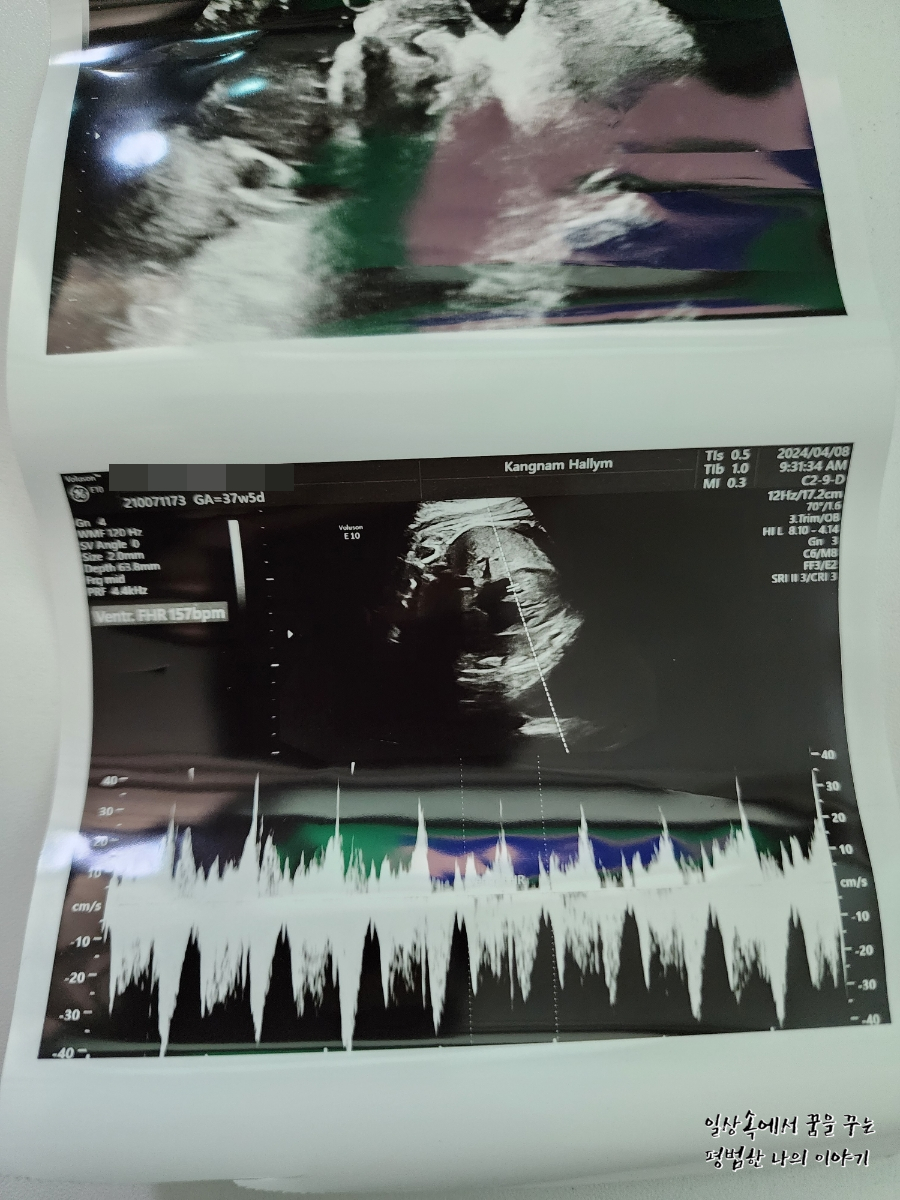

FHR(Fetal Heart Rate, 심장박동 수): 157bpm

2024년 4월 8일(월요일)

GA(Gestational Age, 임신 주차): 37주 차 5일